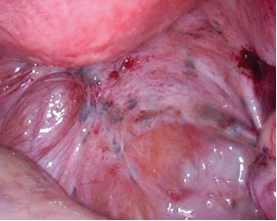

LNMTC phúc mạc mức độ tối thiểu (độ I) |

LNMTC phúc mạc mức độ nhẹ (độ II) |

LNMTC phúc mạc mức độ vừa (độ III) |

LNMTC phúc mạc mức độ nặng (độ IV) |